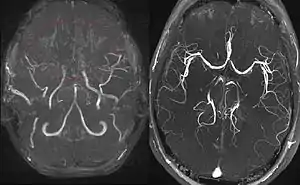

Right: healthy patient, for comparison.

Cerebral angiography is the gold standard of diagnosing moyamoya disease and its progression. According to Suzuki's system, it can be classified into six stages:[15]

Magnetic resonance angiography (MRA) is also useful in diagnosing the disease with good correlation with Suzuki's grading system.[15]